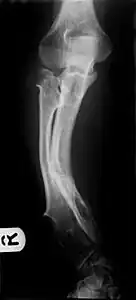

Hereditary multiple exostoses a) Multiple exostoses of the lower limbs b) osteochondromas of the upper limbs

A noticeable lump in relation to an extremity may be the first presenting symptom. Multiple deformities can arise, namely coronal plane deformities around the knees, ankles, shoulders, elbows, and wrists. For example, genu valgum (knock knees), ankle valgus, ulnar bowing and shortening, and radial head subluxation are encountered. The majority of affected individuals have clinically manifest osteochondromas around the knee. Forearm involvement in HMO is considerable.[1][4] Furthermore, short stature may occur and is generally disproportionate. Such manifestations usually result from disruption of physeal growth especially that osteochondromas typically arise at the metaphyseal ends of long bones in close proximity to the physis.[1][4] Intra-articular osteochondromas of the hip can induce limitation of range of motion, joint pain and acetabular dysplasia.[2] Likewise joint pain at other locations and neurovascular compression can occur. Furthermore, functional disability in regard to activities of daily living can be a presenting feature. Spinal deformity pain or neurological compromise should arouse suspicion of involvement of the vertebrae.[3]